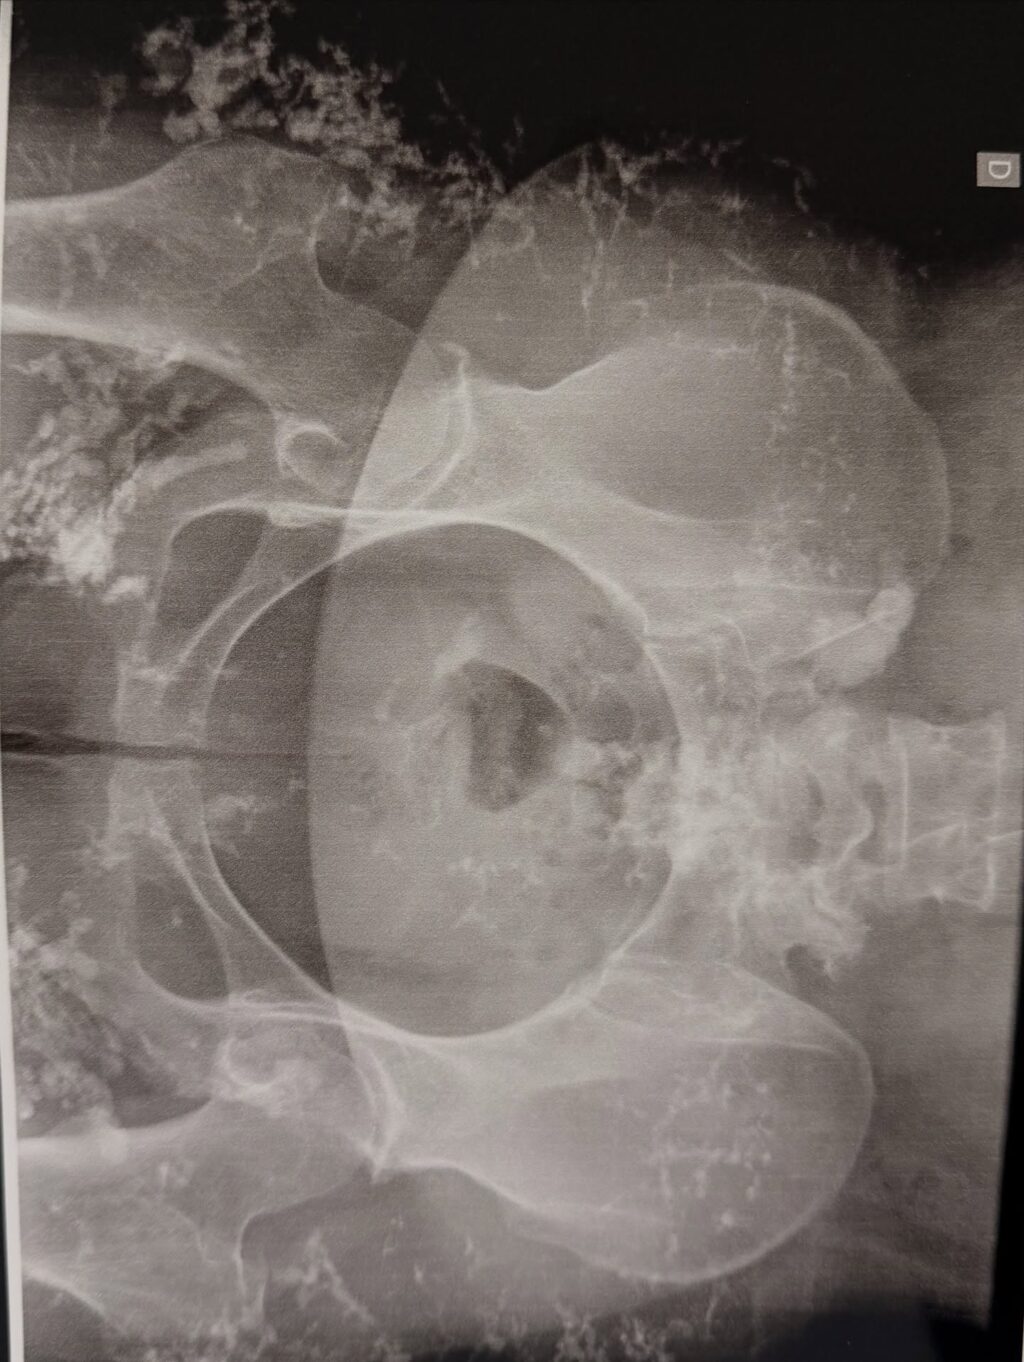

ÁREAS DO CORPO QUE PODEM SER AFETADAS

Entenda onde a Gota afeta seu corpo e como vamos te ajudar

Se você se identificou com as dores intensas e as limitações que a gota impõe, saiba que essa doença pode atacar não apenas o dedão do pé, mas diversas outras articulações, tornando cada movimento um desafio diário.

A dor no dedão do pé é o “cartão de visitas” da gota, conhecida como podagra. É uma inflamação súbita e intensa que transforma um simples caminhar em uma tortura. A articulação fica inchada, quente e sensível a qualquer toque, até o lençol da cama.

A dor intensa, o inchaço e a dificuldade de apoiar o pé no chão tornam atividades como andar, subir escadas ou se equilibrar um desafio doloroso. Essa dor na locomoção impacta sua rotina diária, desde o simples ato de ir à padaria até passeios em família, roubando sua liberdade de movimento e forçando você a depender de outros ou a limitar suas atividades.

Articulação do joelho é um alvo comum para a gota, gerando dores agudas, inchaço e rigidez que dificultam dobrar e esticar a perna. Levantar-se de uma cadeira, agachar ou praticar exercícios se tornam tarefas árduas.

São acúmulos de cristais de ácido úrico que formam nódulos sob a pele, geralmente perto das articulações (orelhas, cotovelos). Além do desconforto físico, podem causar deformidades e constrangimento social. Sua presença indica que a gota não está bem controlada.